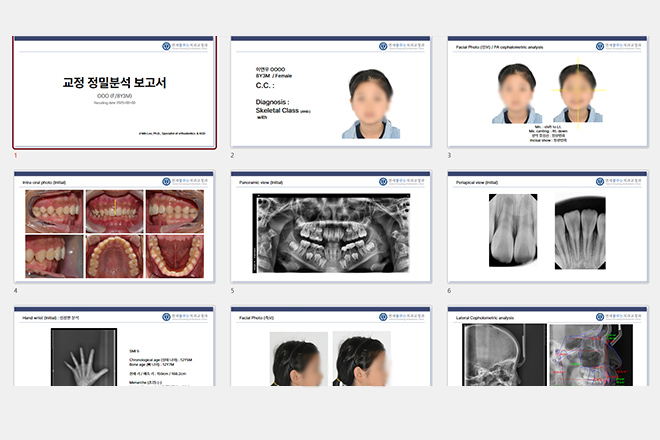

이지민 대표원장이 공동 연구한 AI 기반 성장판 분석 논문의 학술적 근거를 바탕으로,

정밀 성장판 검사 프로그램을 통해 성장기 아동의 성장 페이스를 정확히 예측하고

최적의 교정 시기와 치료 계획을 설계합니다.

3~6개월에 한번씩 진행과정에 대한 정밀분석과 상담을 통해

환자의 현재 성장단계와 향후 잔여 성장을 확인하여 적절한 교정시기와 치료 방법을 결정합니다.

정확한 진단을 위해 대학병원 수준 이상의 정밀 검사 시행

대학병원 수준의 재료와 장비 기준을 그대로 적용

세브란스 병원 교수 출신 대표원장 교정진료